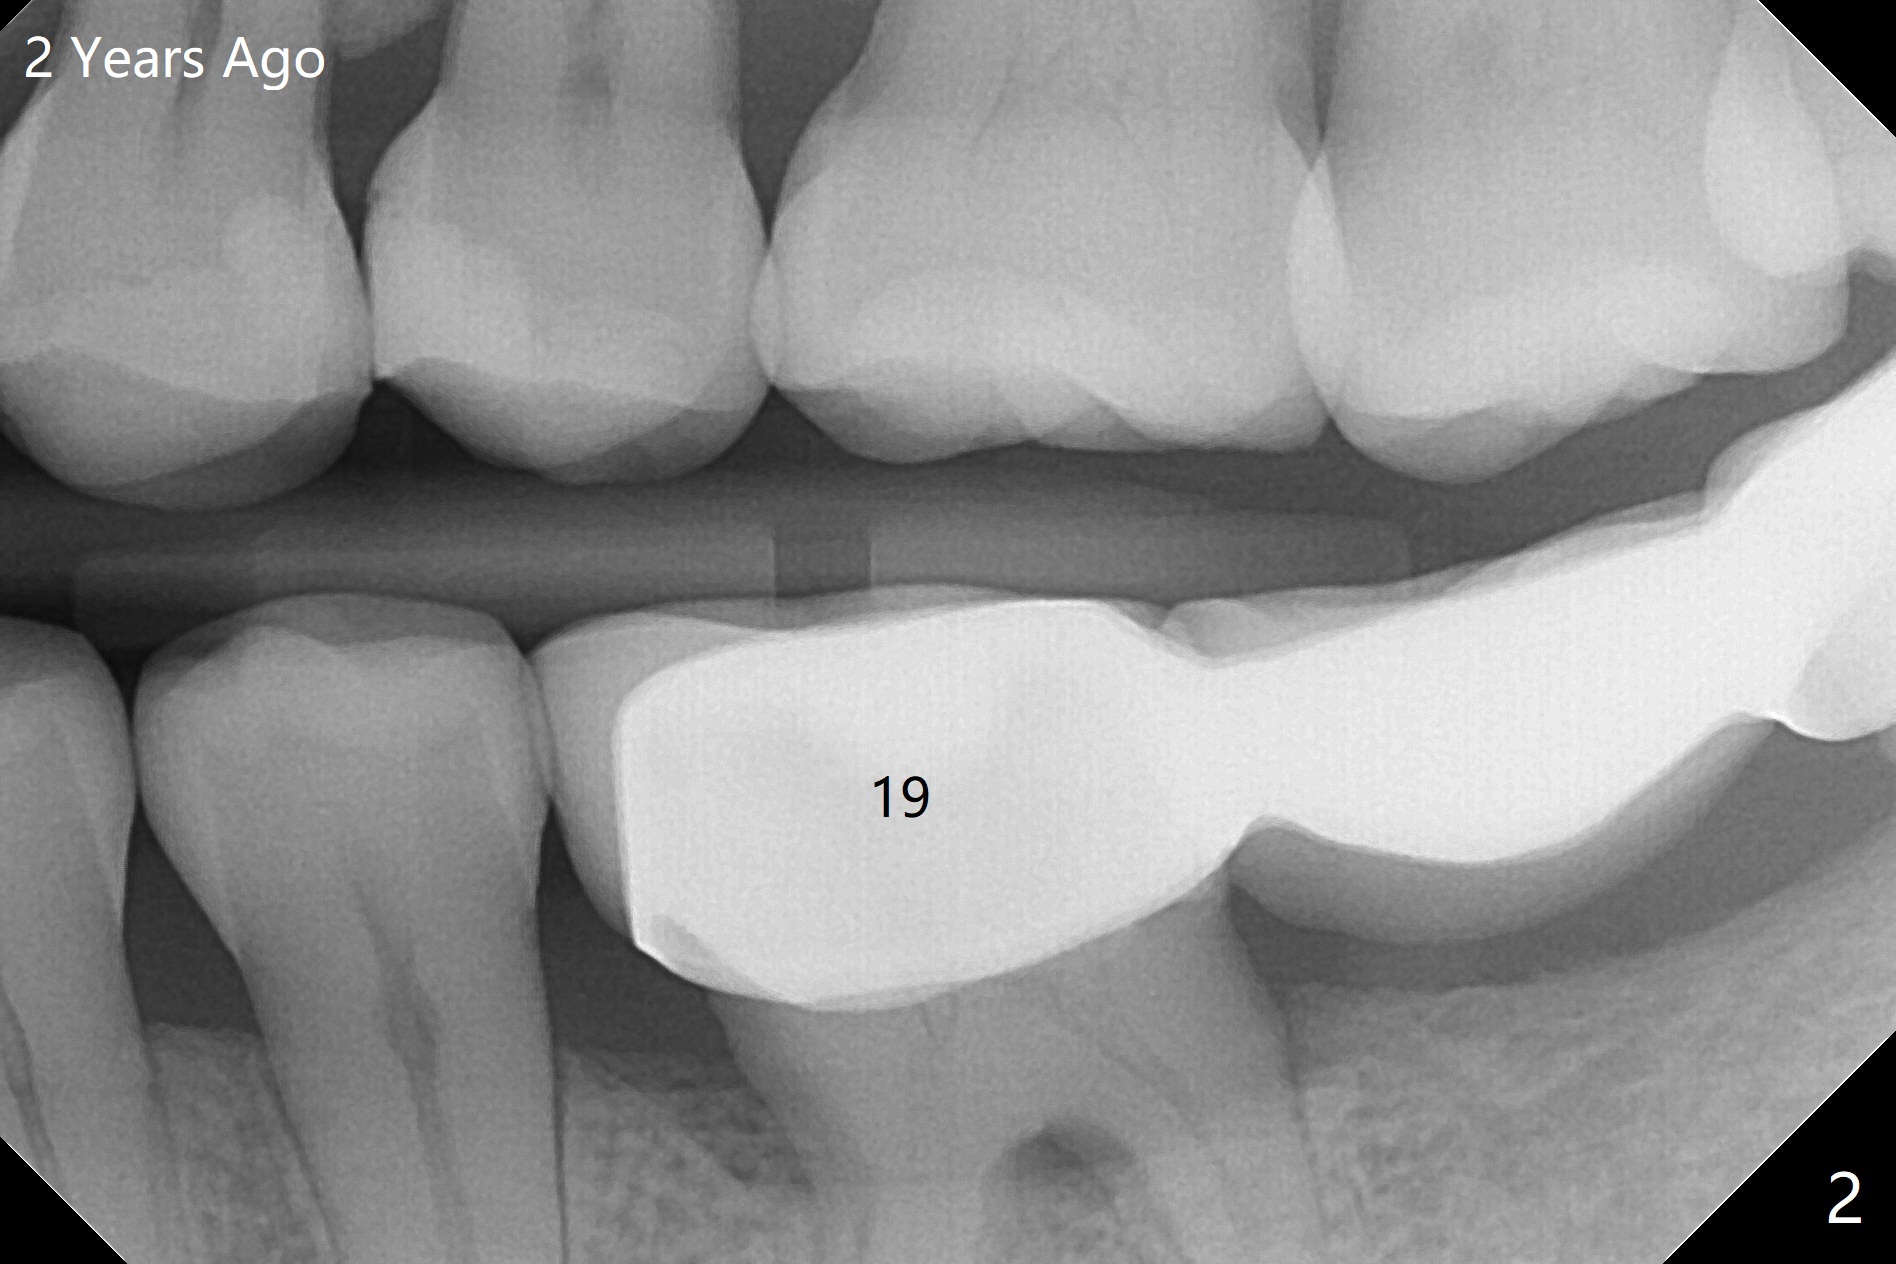

A 35-year-old woman has had guide

Return to No Caries Placement